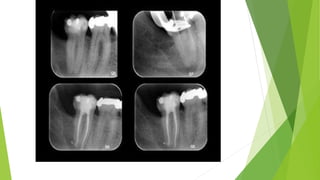

ACUTE APICAL ABSCESS

CLINICAL FEATURES

HISTOPATHOLOGICAL FEATURES OF

 Zone of liquefaction composed of

Exudates

Necrotic tissue

Dilated neutrophils

 Dilated blood cells

 Inflammatory

granular cells infiltration